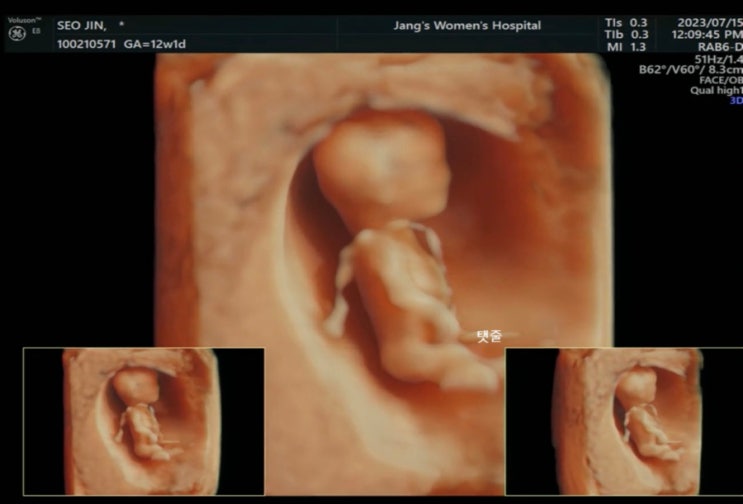

임신 그리고 입덧 지옥의 시작

2022년 10월 22일 결혼을 하고 23년 2월에 스키장에서 발목 골절 부상으로 인하여 2달을 고생한 후 드디어 ...